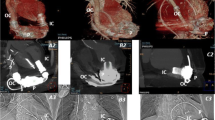

RVEF was calculated by performance of computer contouring of the right ventricle in the RAO 30° position throughout the cardiac cycle and computer detection of the end diastole (ED) and end systole (ES) frames. Right ventricular contouring was performed by identification of the tagged RBC within the RV cavity and contouring of the endocardial border of the RV while excluding the right atrium and main pulmonary artery (Fig. 1). LVEF was calculated by the MUGA portion of the examination that was performed in a similar fashion by contouring the endocardial border of the LV throughout the cardiac cycle in either the LAD 45° or 70° projection given the anatomic position of the heart, and computer detection of ED and ES. All contouring was performed an experience nuclear technologist, and two fellowship trained nuclear medicine radiologists confirmed exam quality and interpreted the FPRNA and MUGA images. The results were obtained retrospectively and were not reinterpreted.

Images of end diastole (ED) and end systole (ES) from a first pass radionuclide angiography. Images were obtained in the 30° RAO position, and computer contouring of the right ventricle was manually performed (yellow dashed line). Attention to including the right ventricular outlow tract to the pulmonary valve (red arrow) and base of the right ventricle to the right atrium (blue arrow) was performed